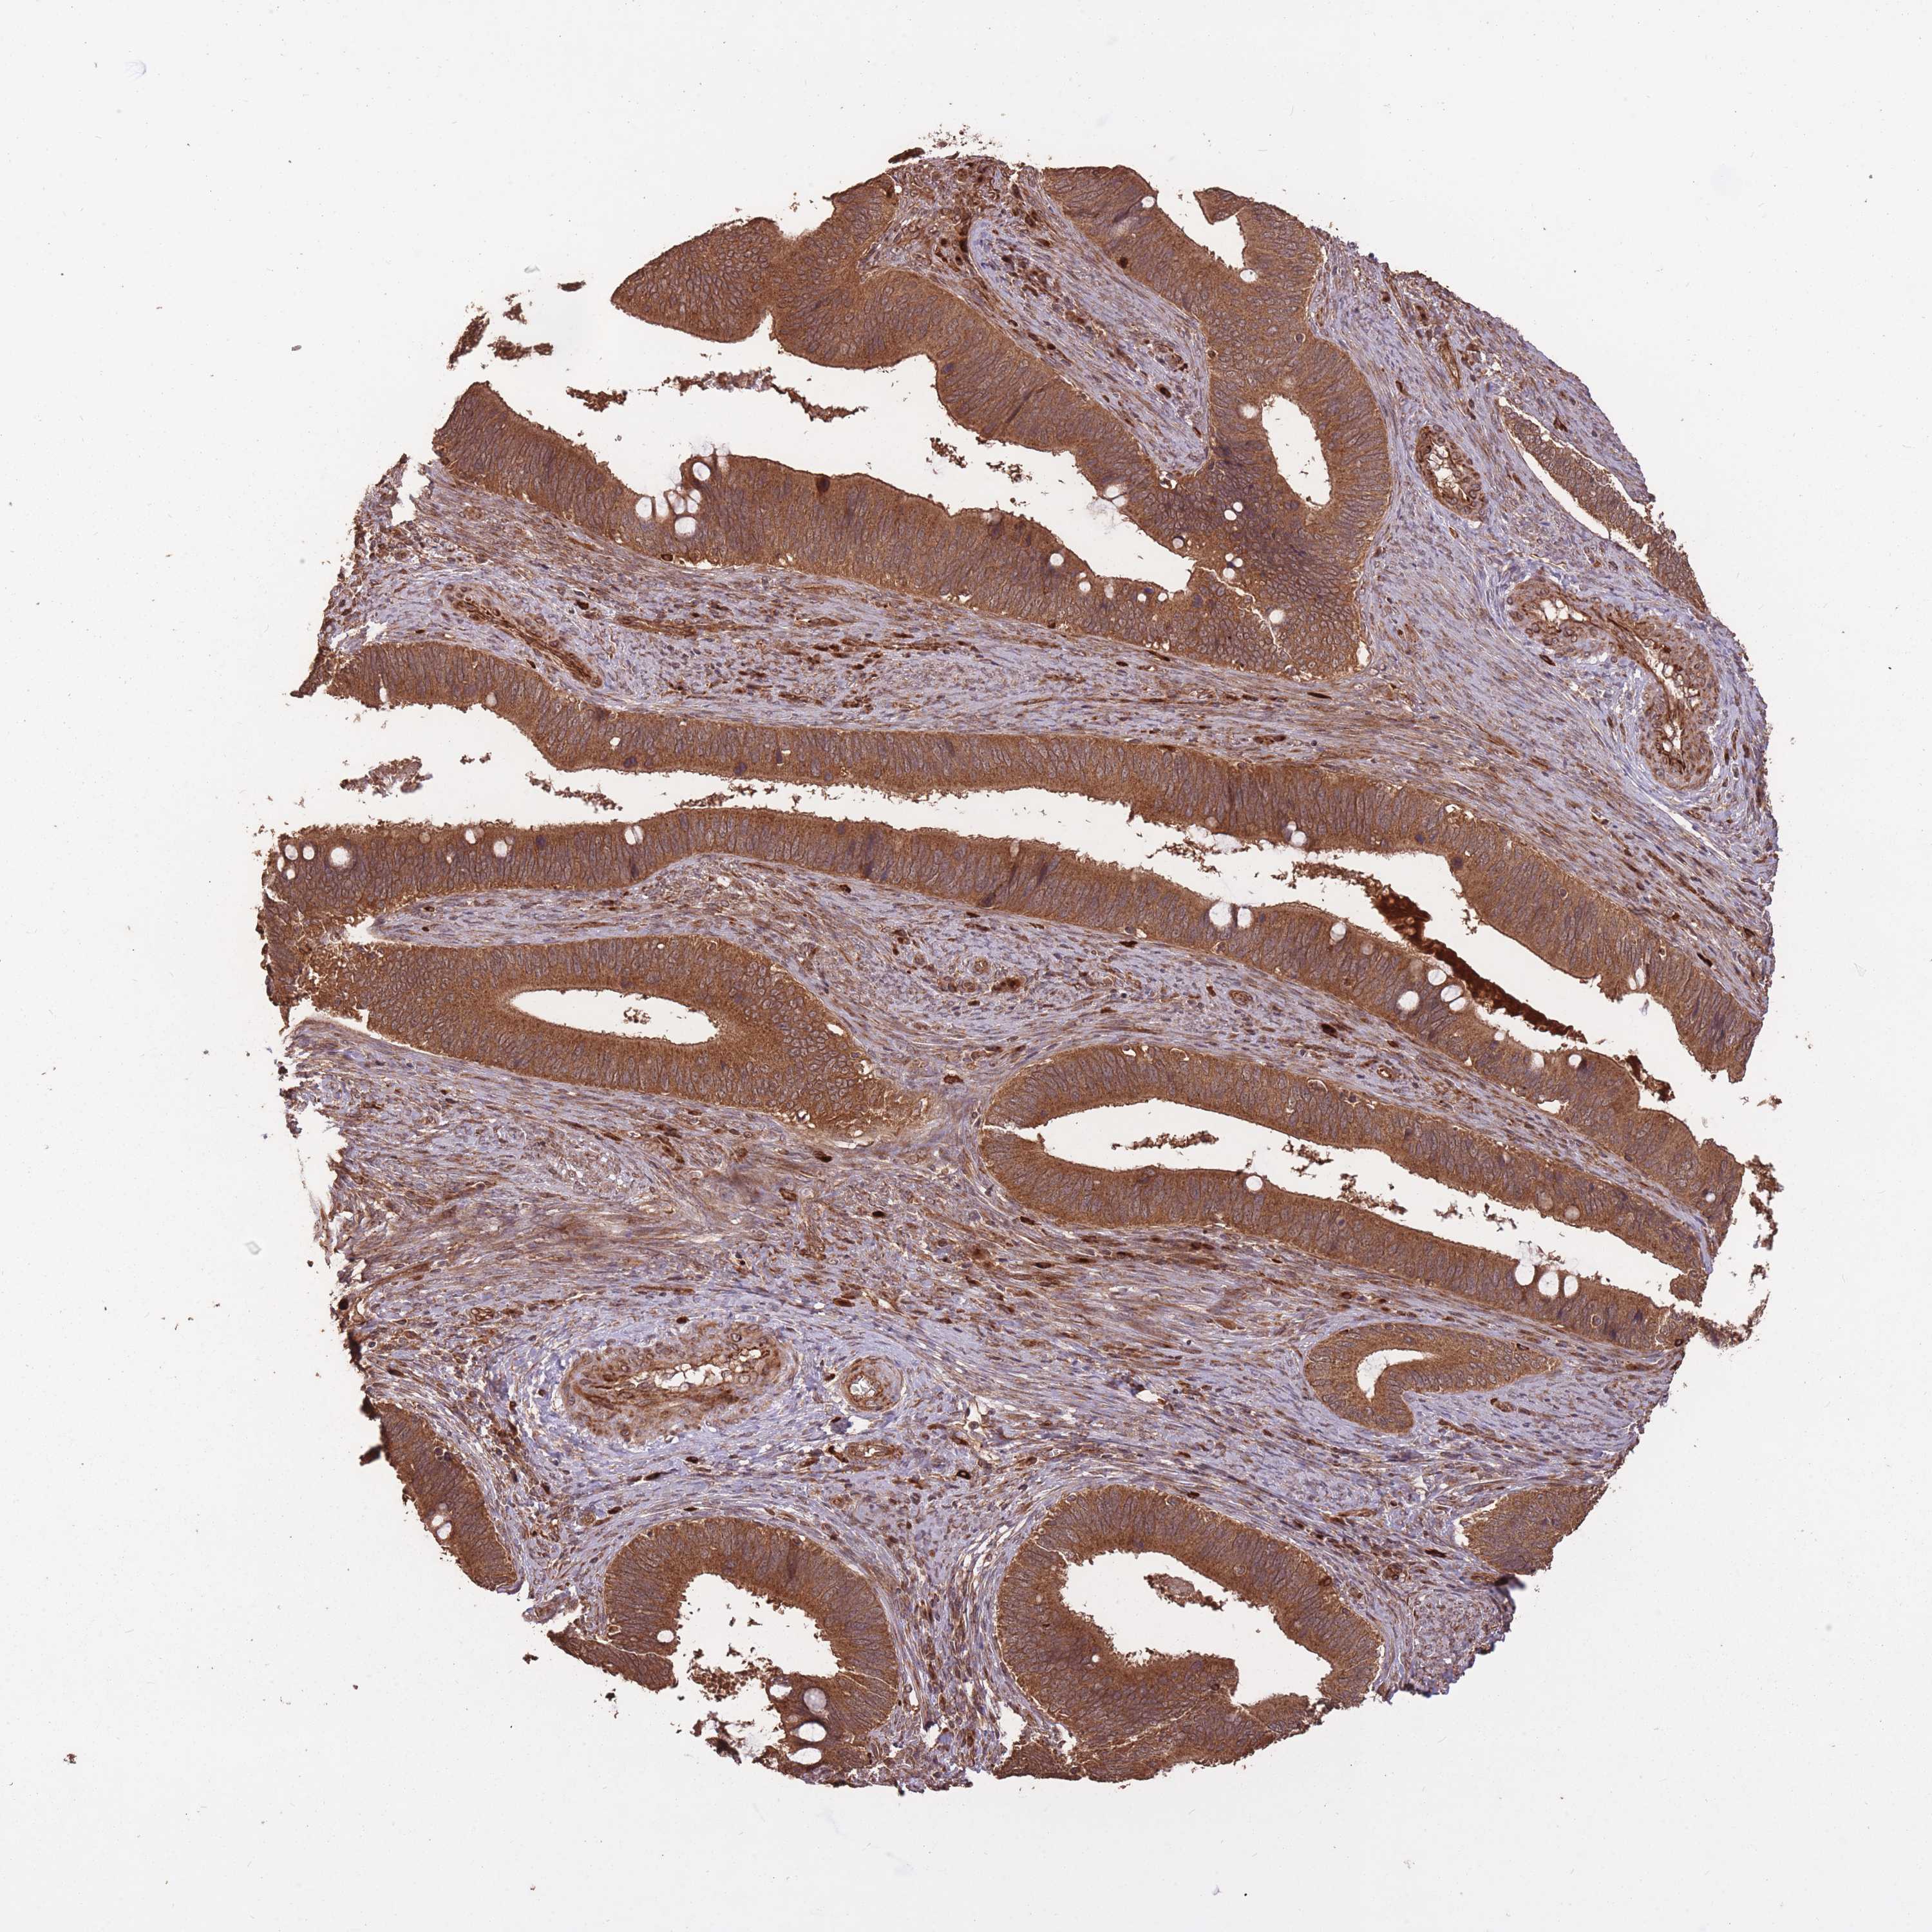

CERVICAL CANCER - Protein expressioni

A mouse-over function shows sample information and annotation data. Click on an image to view it in a full screen mode. Samples can be filtered based on level of antibody staining by selecting one or several of the following categories: high, medium, low and not detected. The assay and annotation is described here.

Note that samples used for immunohistochemistry by the Human Protein Atlas do not correspond to samples in the TCGA dataset.

Antibody stainingi

Antibody staining in the annotated cell types in the current human tissue is reported as not detected, low, medium, or high, based on conventional immunohistochemistry profiling in selected tissues. This score is based on the combination of the staining intensity and fraction of stained cells.

Each image is clickable and will lead to virtual microscopy that enables deeper exploration of all samples and also displays staining intensity scores, fraction scores and subcellular localization as well as patient and tissue information for each sample.

Antibody HPA045396

Antibody HPA070524

Antibody CAB025331

Squamous cell carcinoma, NOS

Adenocarcinoma, NOS